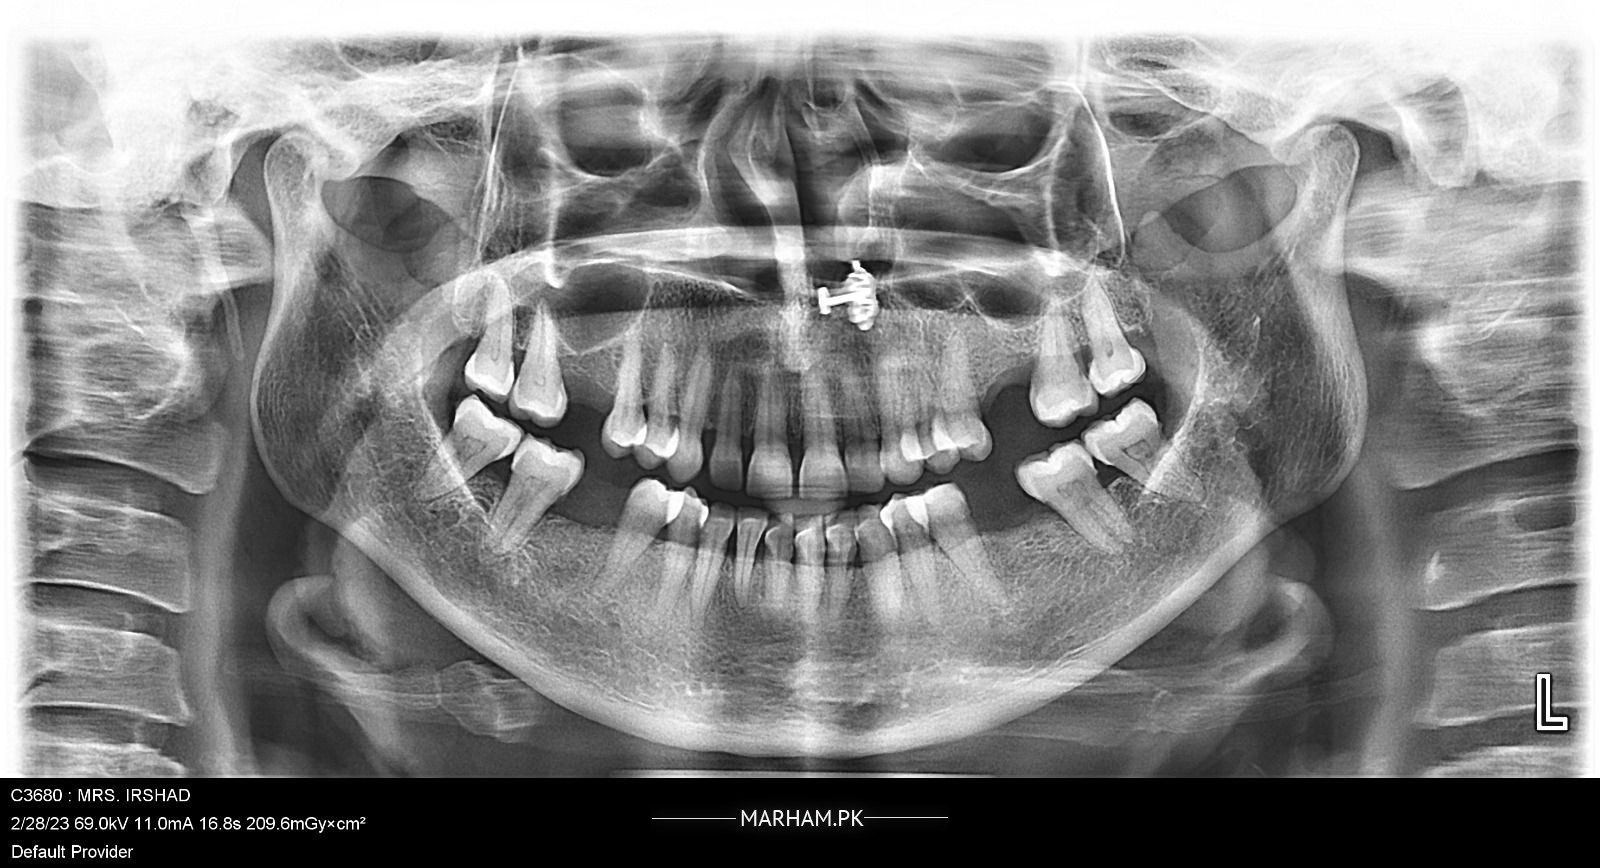

Mari mama k gums ma abnormal skin growth hai shaid swelling hai mouth opening b Kam hai Samaj nae a raha Kya kea jay Kai doctors ko check krwaya unho na medication ki but problem still the same koi advise kr day k kia krna chaiay x ray or gums ki pic attach krdi hai

there could be some periapical infection, visit the nearby dentist and get the x ray done, so that more precised treatment plan can be decided.

It seems to be traumatic gingivitis which is due to supra eruption of upper molar tooth into the lower edentulous space. Root canal treatment of upper molar tooth. Then it will be trimmed to the level occlusal plan. And prosthesis to be given in the lower edentulous space